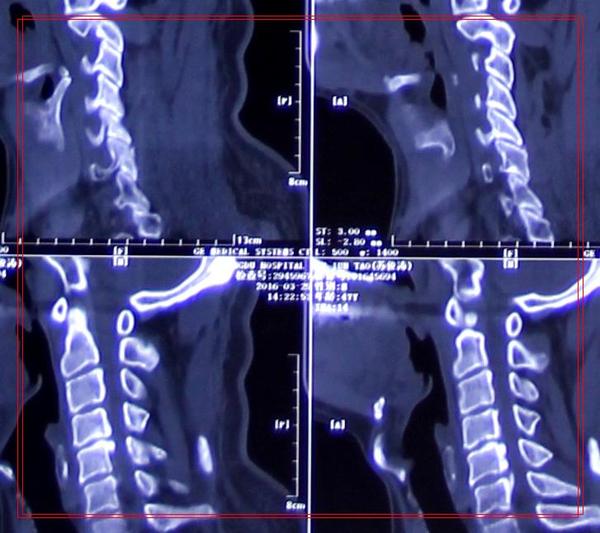

影像学资料